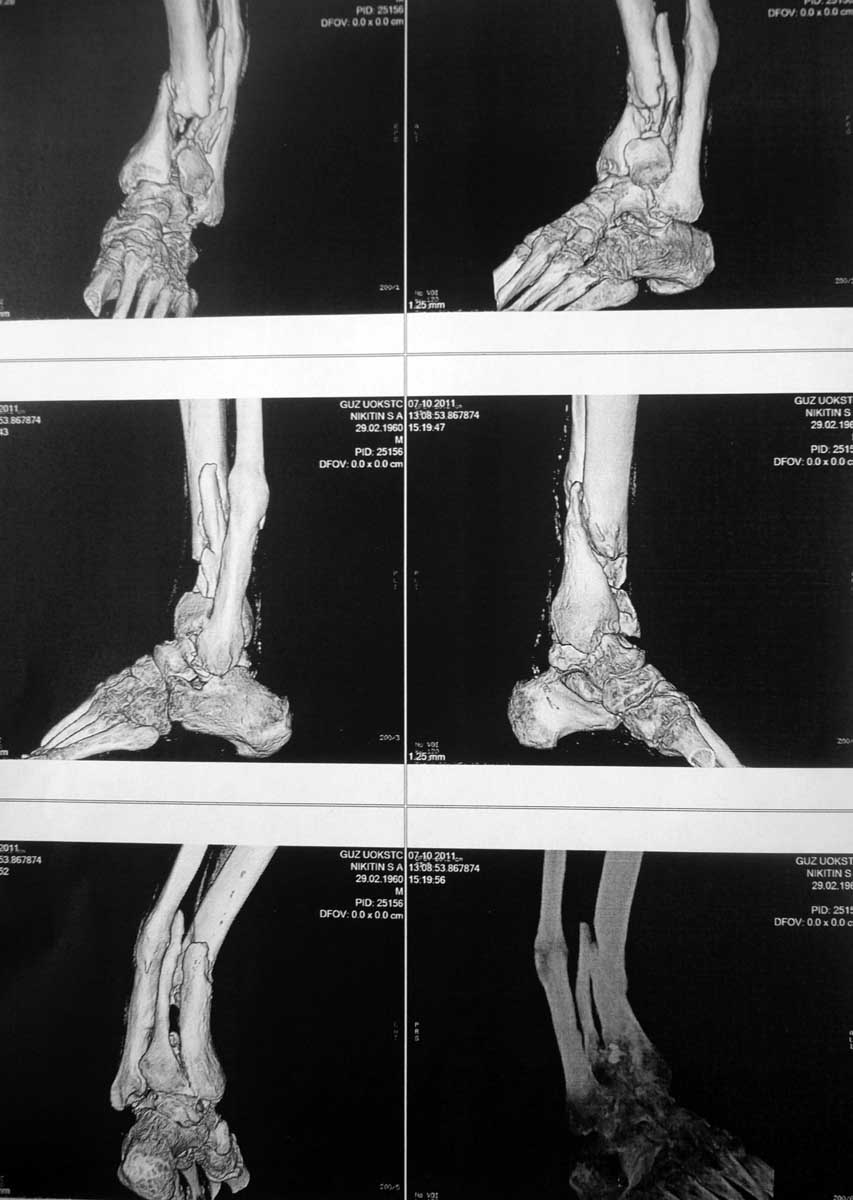

Для определения деформации длинных костей полезны обычные рентген снимки, а 3D снимки, оставаясь красивой картиной снаружи, не дают полную информацию про то, что внутри сустава. В дальнейшем необходимость исследования на КТ будет, но для выработки тактики помогут поперечные и сагиттальные срезы. На всю конечность длинные снимки помогут сделать расчет угла деформации, и прицельный снимок голеностопа оценит сустав.

На 3D снимке виден большой фрагмент в переднем отделе, а поперечные КТ срезы уточнят точную топографию фрагментов. Возможно, основной фрагмент только спереди, и реконструкцию можно делать из переднего доступа с артротомией. Любая передняя длинная пластина (предпочитаем DePuy) с костным графтом и коррекция малоберцовой из латерального доступа. Тенденцию варуса можно устранить временным на три недели медиальным наружным фиксатором со стержнями в пятке и голени.